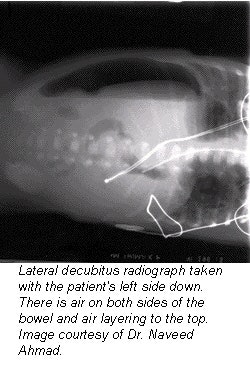

Left lateral decubitus AP abdominal exam

- Lateral decubitus position and cross table lateral films: If the patient is unable to stand, a film of the patient in the lateral decubitus position should be obtained with a horizontal beam. This method results in less penetration of the abdominal viscera but good visualization of small amounts of extra alimentary gas. Alternatively, this information can be obtained on a film of the abdomen taken with the patient in the dorsal decubitus position. This position is usually adequate in providing the required image and should be used in patients where an upright position film is impractical.